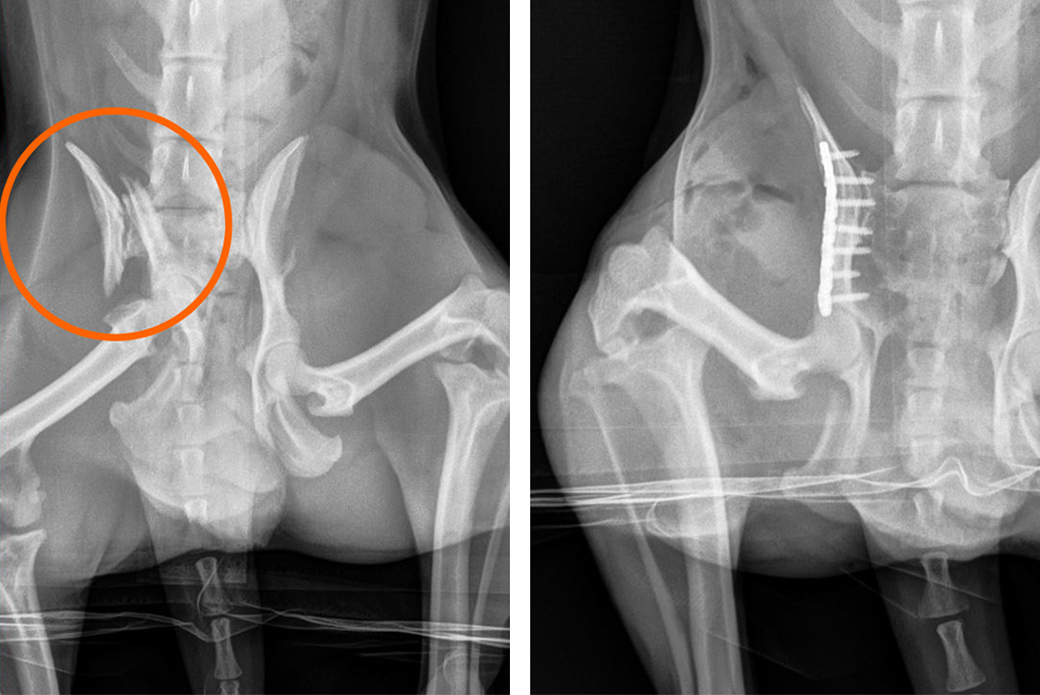

At the vet, X-rays revealed fractures on the right side of Rocky’s pelvic bone. The veterinarian prescribed pain medication and cage rest.

“Rocky had a high-impact pelvic fracture that caused his pelvis to break in five places,” says Dr. Matthew Morgan, VERG Chief of Surgery who performed Rocky’s surgery. “The injuries were severe due to the orthopedic and soft tissue trauma that occurred around his pelvis, causing it to essentially shatter. Many patients with this type of high-impact injury do not survive the initial impact long enough to be brought to a vet. Rocky was an exception and a very tough dog.”

Dr. Morgan placed a titanium bone plate with screws along the right side of Rocky’s pelvis to reconstruct the bones so that they would be able to bear weight.